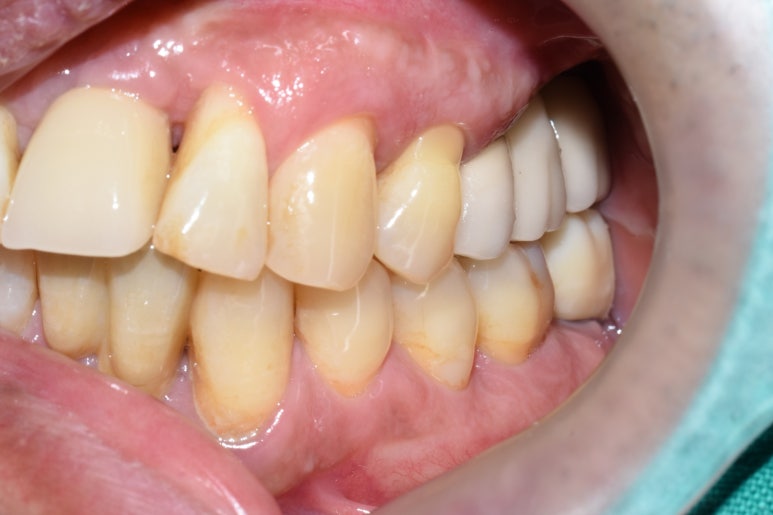

그래서 임플란트 픽스쳐를 제거하고,

옆의 흔들리는 치아 하나 까지 발치하여

임플란트 재수술은 임플란트 2개를 심고 머리 3개를 만들어 완성하였습니다.